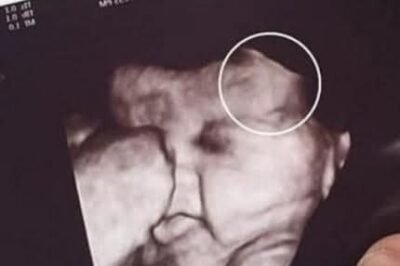

routine prenatal checkup took an unexpected turn for one mother after she grew visibly anxious during her daughter’s ultrasound appointment….